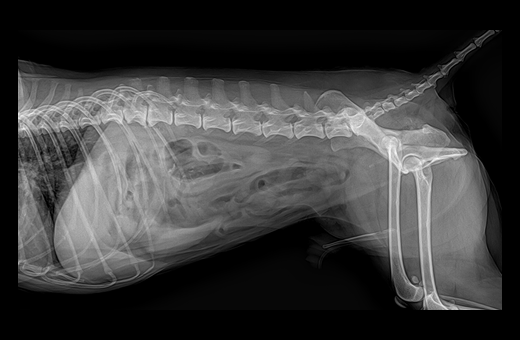

음경 요도(penile urethra)에 걸린 결석 2

· 방사선 검사

배뇨 곤란으로 내원하게 되면 일반적으로 방사선 검사가 가장 우선시 되게 됩니다.

방사선 검사에서는 결석이 어느 위치에 분포되어 있는지, 폐색으로 인한 방광 확장 정도가 어느 정도인지 등을 우선적으로 평가합니다.